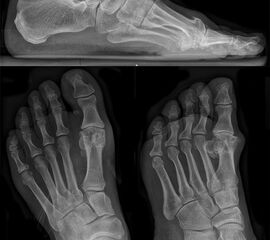

• Röntgen: Fuß belastet in 3 Ebenen.

• Optional MRT und CT bei radiologisch unklaren Verhältnissen.